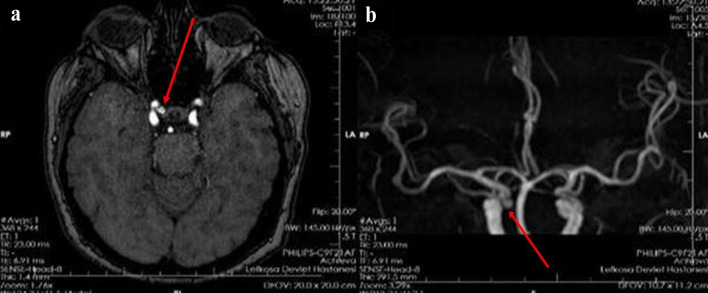

面肌痉挛(HFS)是一种神经系统疾病,其特征是面部一侧面神经支配的肌肉不自主、阵发性收缩。虽然原发性HFS最常由面神经根出口区(REZ)的血管压迫引起,但继发原因如肿瘤、动静脉畸形和颅内动脉瘤是罕见的。由于动脉瘤压迫导致的HFS的治疗仍然具有挑战性,并且关于血管内治疗的文献,特别是流分流支架的文献是有限的。我们报告一例56岁女性,有2型糖尿病、高血压和高胆固醇血症病史,表现为进行性右侧HFS。影像显示右侧颈内动脉(ICA)在海绵状眼段有囊状动脉瘤。患者成功接受了衍生栓塞装置(DED)血流分流支架的血管内治疗。她的HFS在手术后完全消失,在6个月的随访中没有神经功能缺损或复发。本病例强调了分流支架置入术治疗由ICA囊状动脉瘤引起的HFS的疗效,是北塞浦路斯第一例此类报道。该病例强调了考虑非典型HFS继发病因的重要性,并证明了在这种情况下血管内血流转移的治疗潜力。

Hemifacial spasm (HFS) is a neurological disorder characterized by involuntary, paroxysmal contractions of the muscles innervated by the facial nerve on one side of the face. While primary HFS is most often caused by vascular compression at the root exit zone (REZ) of the facial nerve, secondary causes such as tumors, arteriovenous malformations, and intracranial aneurysms are rare. The management of HFS due to aneurysmal compression remains challenging, and the literature on endovascular treatment, particularly with flow diverter stents, is limited. We report the case of a 56-year-old woman with a history of diabetes mellitus type 2, hypertension, and hypercholesterolemia, who presented with progressive right-sided HFS. Imaging revealed a saccular aneurysm of the right internal carotid artery (ICA) at the cavernous-ophthalmic segment. The patient underwent successful endovascular treatment with a Derivo embolization device (DED) flow diverter stent. Her HFS resolved completely post-procedure, with no neurological deficits or recurrence at 6-month follow-up. This case highlights the efficacy of flow diverter stent placement for HFS caused by ICA saccular aneurysm and represents the first such report from Northern Cyprus. The case underscores the importance of considering secondary etiologies in atypical HFS and demonstrates the therapeutic potential of endovascular flow diversion in this context.